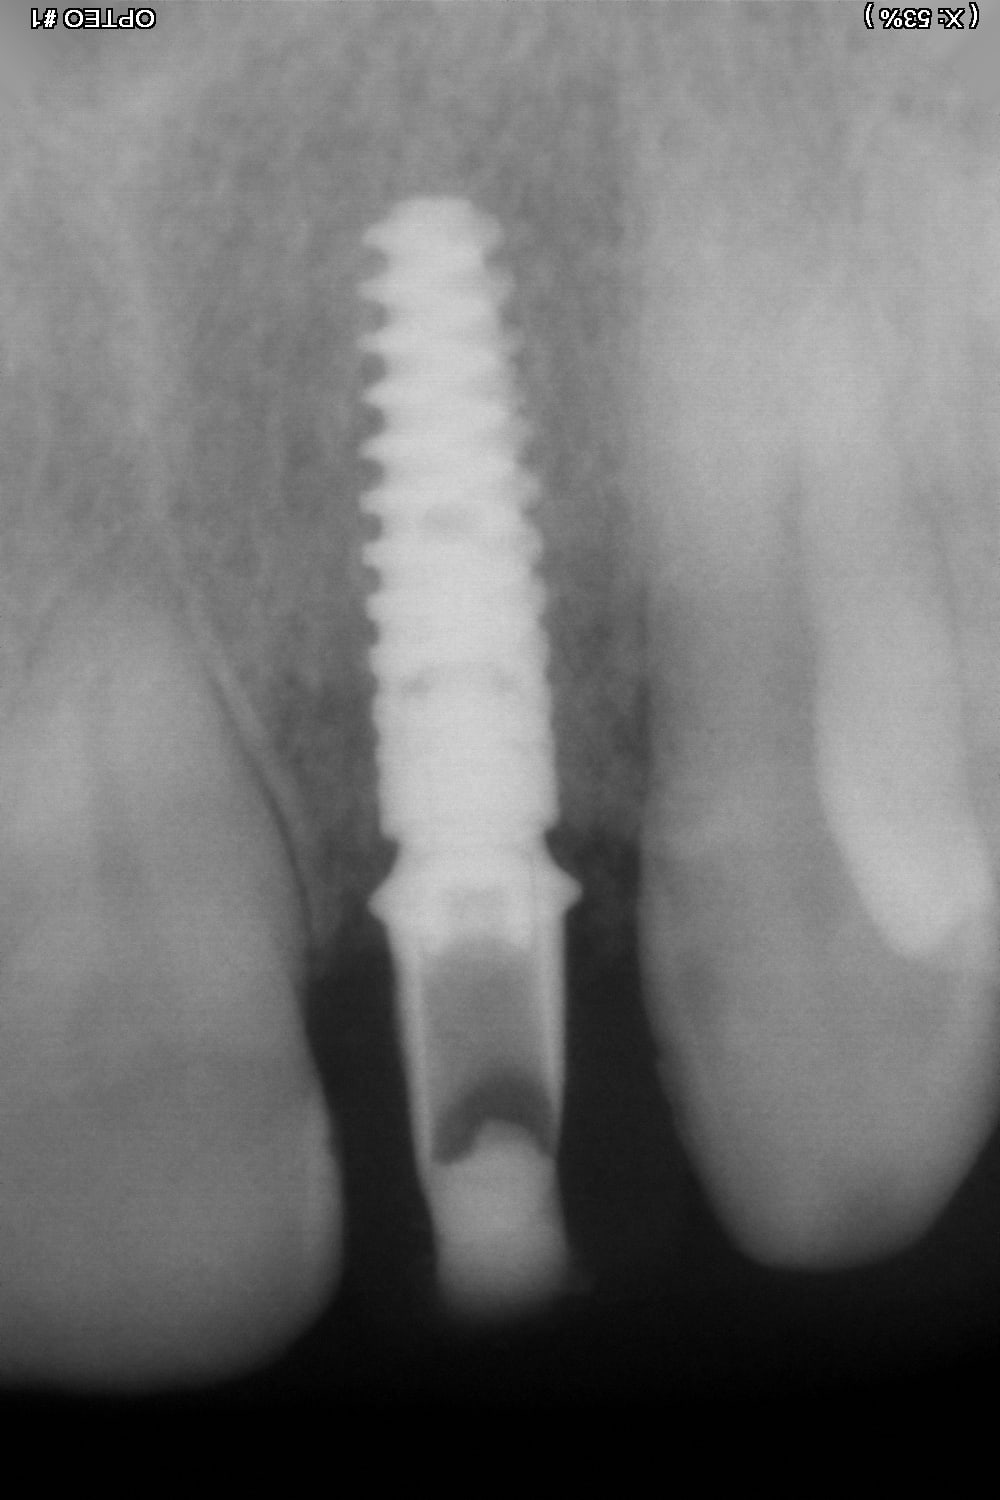

Je n'avais que 6 mm mais pourtant ca passe!